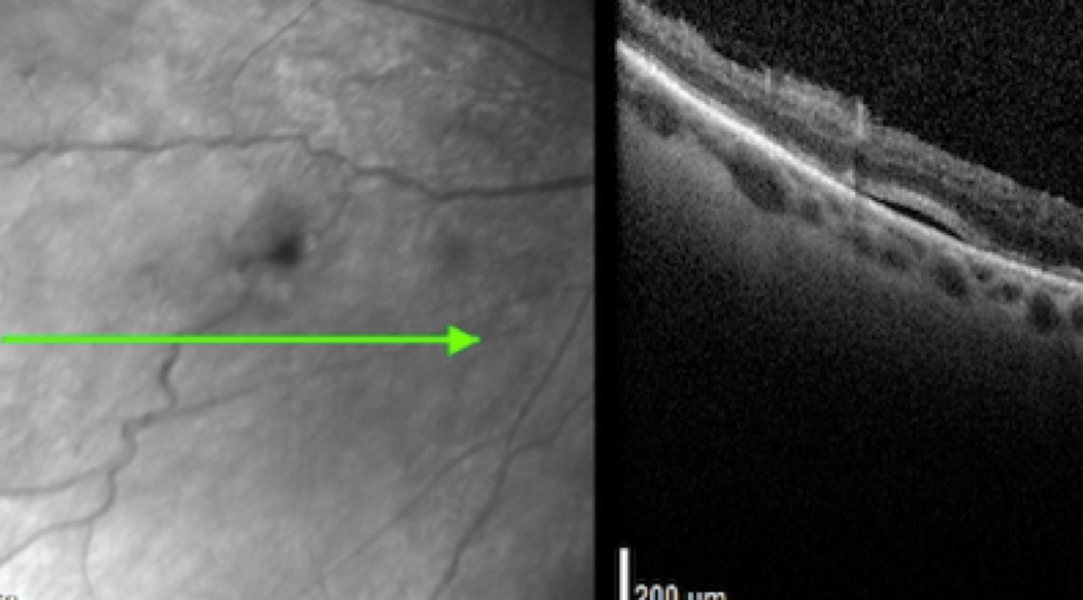

High-definition spectral-domain OCT (SD-OCT) revealed a partial posterior vitreous detachment (PVD) and traction on a vessel leading to the vitreous hemorrhage and a small retinal break (Figure 2). A shallow neurosensory detachment was also noted on imaging (Figure 3).

Figure 3: High-definition spectral-domain OCT OS revealed an isolated shallow area of fluid adjacent to the retinal break.

This case represented a diagnostic challenge. The patient’s spontaneous VH was likely caused by a partial PVD with persistent traction leading to a torn retinal vessel. High-definition SD-OCT revealed an isolated retinal tear with shallow neurosensory detachment in the midperipheral nasal retina. She was referred for urgent evaluation and treated with laser photocoagulation.